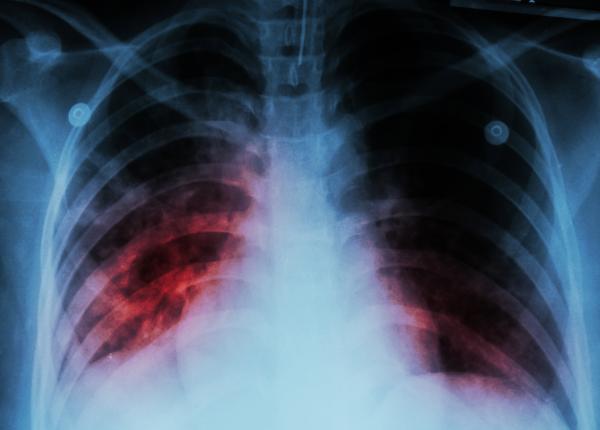

Cancerul pulmonar, boala fără simptome în fazele inițiale. Daniela Nica: Fumătorii au un risc de 30 de ori mai mare de a dezvolta un neoplasm pulmonar

Cancerul pulmonar, cel mai agresiv cancer. Avansează rapid la creier, oase și inimă. Dă metastaze în tot corpul. Testele care pun diagnosticul

Acesta este cel mai agresiv cancer. Avansează ușor la creier, oase și dă rapid metastaze în tot corpul.